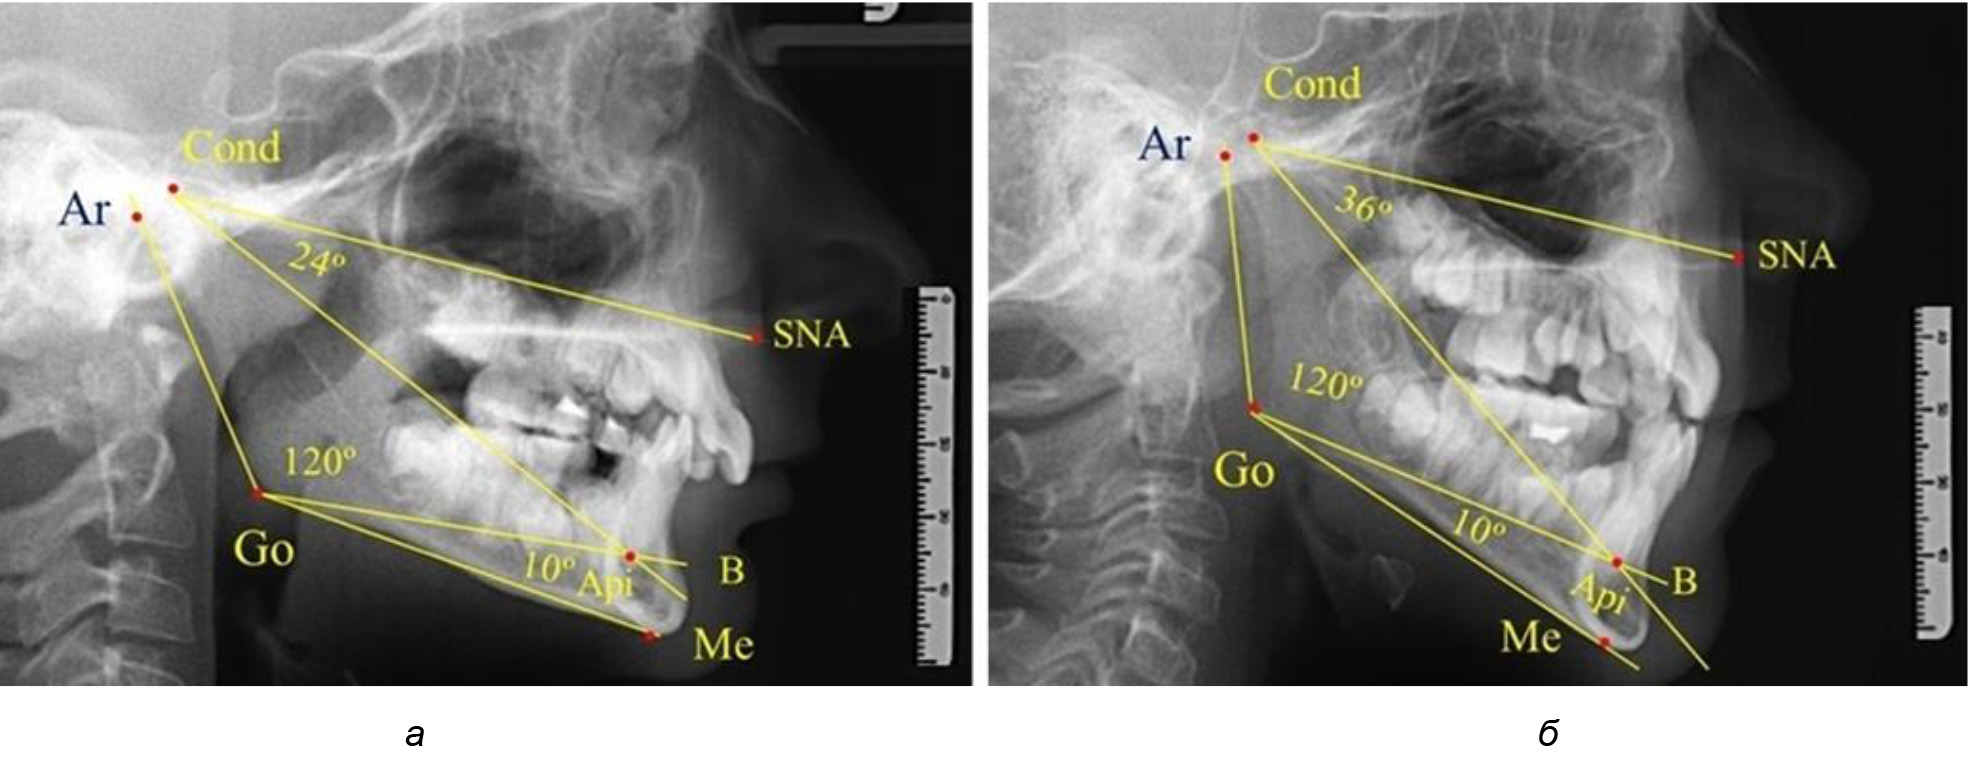

При анализе ТРГ 5 детей в периоде прикуса молочных зубов отмечено, что величина основного угла гнатической части лица SNA-Cond-Api, как правило, в норме составляла около 30°, и его величина была относительно стабильной у всех обследованных детей. В то же время угол нижней челюсти и его составляющие отличались вариабельностью параметров при различных показателях нижнечелюстного угла (рис. 4).

Рис. 4. Особенности ТРГ (а) и 3D-модели (б) в периоде прикуса молочных зубов